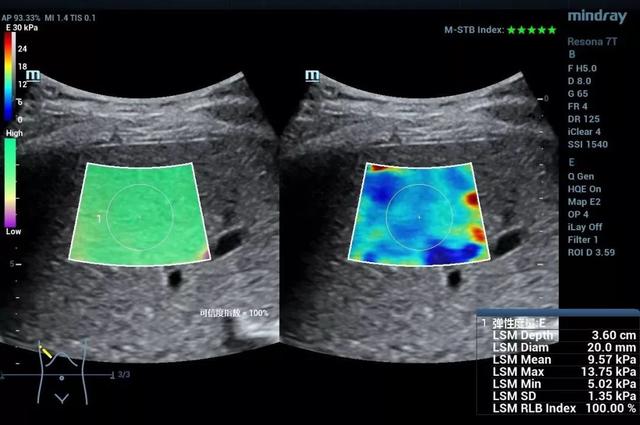

作为一种无创的能够反应组织硬度的功能性成像方法。目前剪切波弹性成像的研究已经涉及肝脏、甲状腺、乳腺、胃肠道、肌骨等方方面面,对于弥漫性病变的分级、局灶性病变的鉴别诊断、疾病的监测及随访等都有重要的意义。例如诊断肝脏纤维化的分期,从F1-F4的图像中,我们发现,尽管二维声像图差别不大,但当纤维化程度增高时,肝脏杨氏模量也增高了,也就是说肝脏“变硬”了。可见,超声发展到这里,不但有形态学上的灰阶超声,血流动力学上的彩色多普勒超声,还有机械力学上的弹性超声。

肝纤维化F3期

肝纤维化F4期